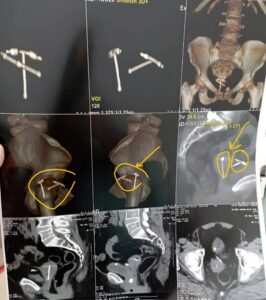

استمرت المريضة في معاناتها لفترة طويلة حتى خضعت لفحوصات دقيقة في مركز طبي متخصص، حيث أظهرت الأشعة المقطعية أن اللولب الأول كان مخترقًا جدار المثانة ومغطى ببعض الحصوات، بينما كان اللولب الثاني موجودًا داخل الرحم، مع حصوات في قناة مجرى البول.

تم إعداد خطة جراحية دقيقة بالتعاون بين استشاريي المسالك البولية وجراحة النساء، تضمنت إزالة حصوات المثانة بالمنظار، ثم فصل اللولب الأول واستئصاله، وإغلاق جدار الرحم والمثانة، وإجراء تدخل لرفع اللولب الثاني عبر فتحة أمامية للرحم. بعد الجراحة المعقدة، خرجت المريضة من المستشفى بصحة جيدة، مؤكدة نجاح الفريق الطبي بقيادة د. أمير فايق، استشاري جراحة ومناظير الكلى والمسالك البولية، وفريق العمل المساعد.